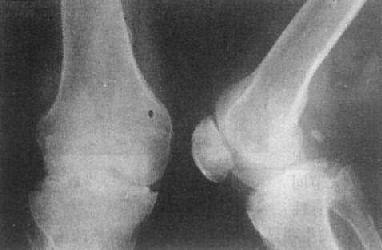

关节退行性变的早期X线表现主要是骨性关节面模糊、中断、消失。中晚期表现为关节间隙狭窄、软骨下骨质囊变和骨性关节面边缘骨赘形成,不发生明显骨质破坏,一般无骨质疏松。

这种变化多见于老年,以承受体重的脊柱和髋、膝关节为明显(图2-1-15、16),是组织衰退的表现。此外,也常见于运动员和搬运工人,由于慢性创伤和长期承重所致。不少职业病和地方病可引起继发性关节退行性变。

图2-1-16 关节退行性变-膝关节退行性骨关节病

膝关节的关节间隙变窄,边角锐利,有骨赘形成,关节面平而致密